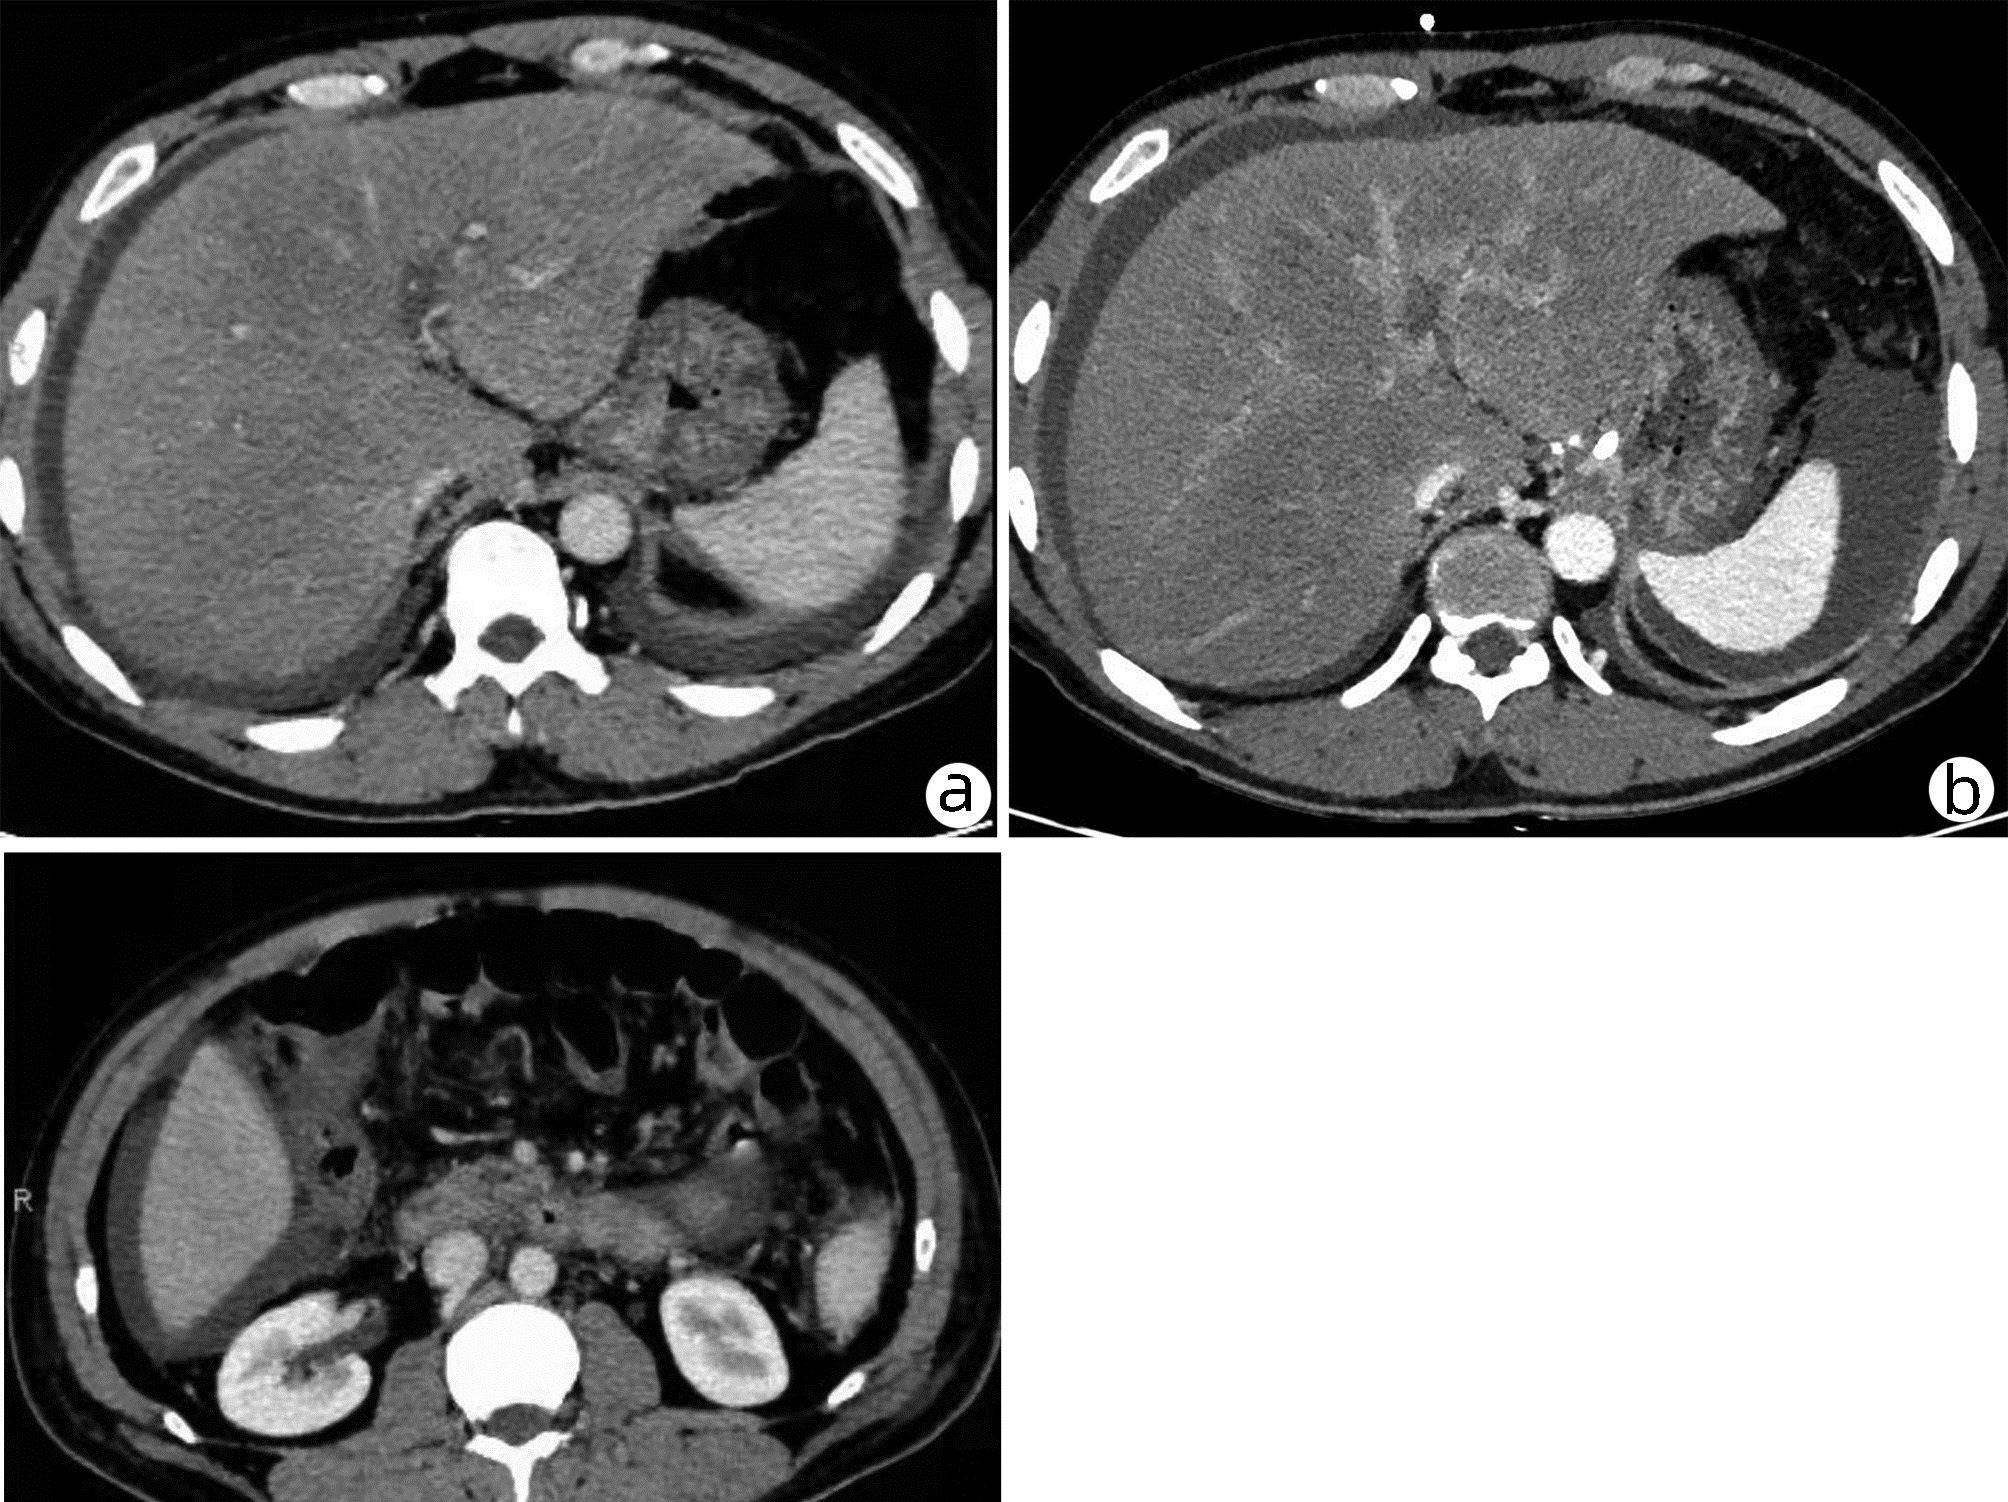

肝窦阻塞综合征合并胰周积液误诊为急性胰腺炎1例报告

陈佼舜, 张浩翔, 殷涛

2022, 38(10): 2341-2343. DOI: 10.3969/j.issn.1001-5256.2022.10.026

摘要(874) HTML (241) PDF (2266KB)(78)

摘要: